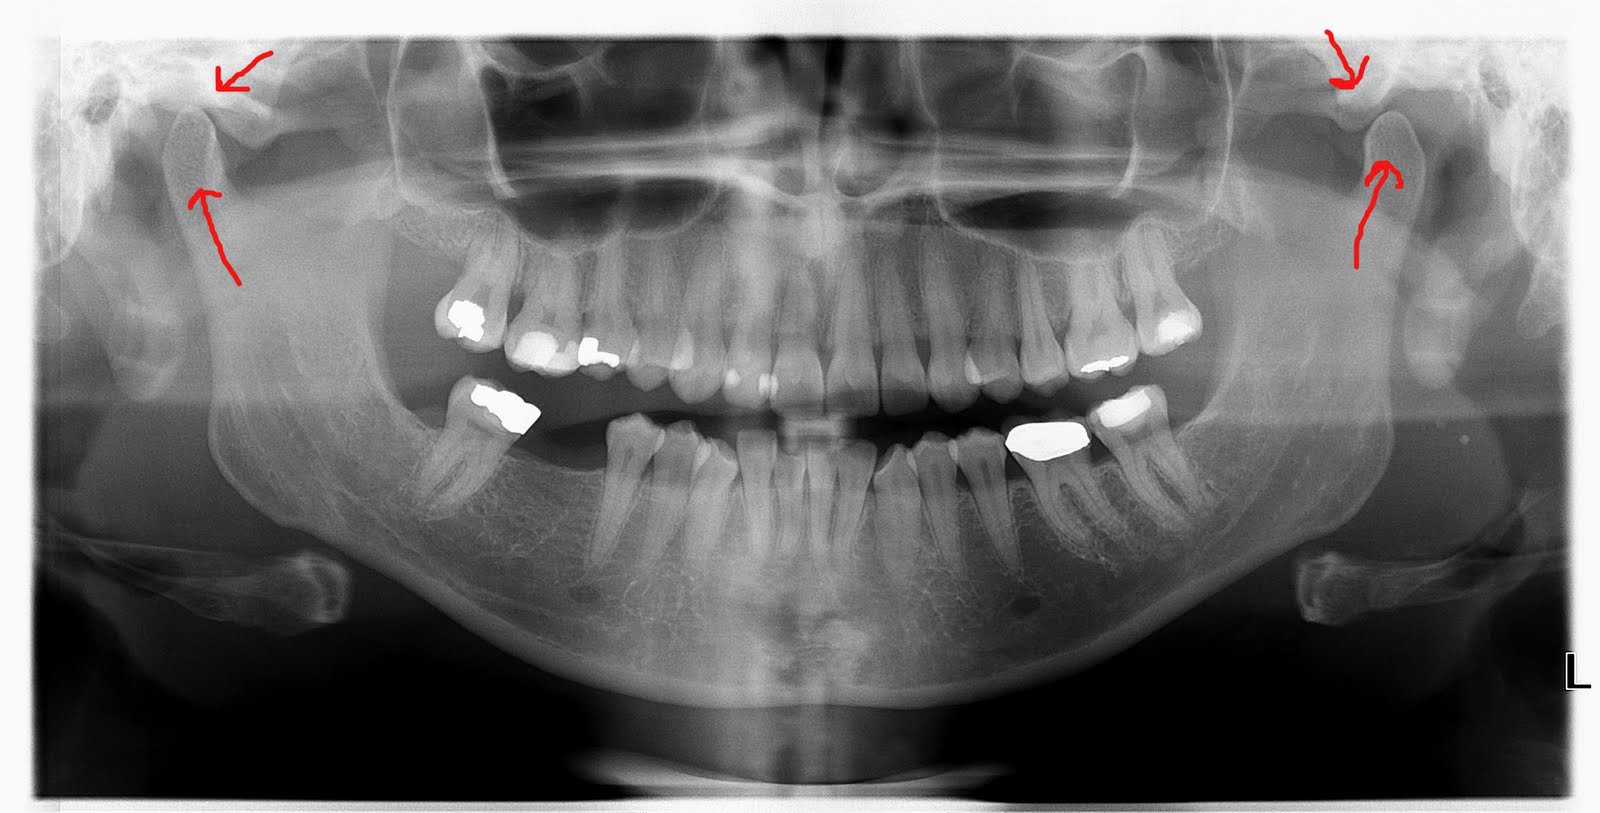

XRay of total TMJ replacement and upper jaw surgery. jawsurgery

XRay of total TMJ replacement and upper jaw surgery. jawsurgery Normal Jaw Bone X Ray It occurs when specialized cells, called osteoclasts break down bone tissue and dissolve the bone matrix. However, it is important to inform your dentist. It is important for radiologists to recognize the indications and appropriate imaging studies for various jaw lesions. This normal physiological process maintains bone remodeling and helps to regulate calcium levels in the body. The mandible can. Normal Jaw Bone X Ray.